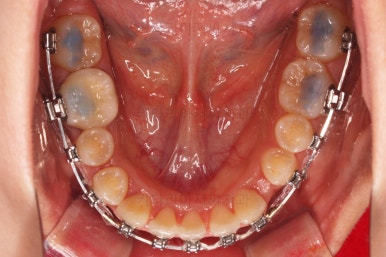

아래 앞니 3개인 채로 마무리를 하기도 하고 4개처럼 보이게끔 마무리를 하기도 합니다.

이번 환자분의 경우는 치아 크기와 비율, 교합 등을 전반적으로 고려해서 아래 앞니가 마치 4개인 것처럼 마무리를 하기로 했습니다.

뒤쪽 치아를 차례차례 끌고 당겨와서 앞니를 대신하는거죠.

물론 기간은 많이 걸리나 현재로서는 가장 합리적인 방법으로 판단했습니다.

이제는 아래 앞니가 3개이기 때문에 생기는 중앙선의 문제, 치아 갯수의 문제를 맞춰나가기로 했습니다.

계획은 오른쪽 아래 송곳니 ~ 어금니 모든 치열을 앞쪽으로 밀어줘 아래 앞니를 마치 4개인 것처럼 만드는 것입니다.

중앙선을 맞추고 교합도 잘 맞추고 마무리를 합니다.